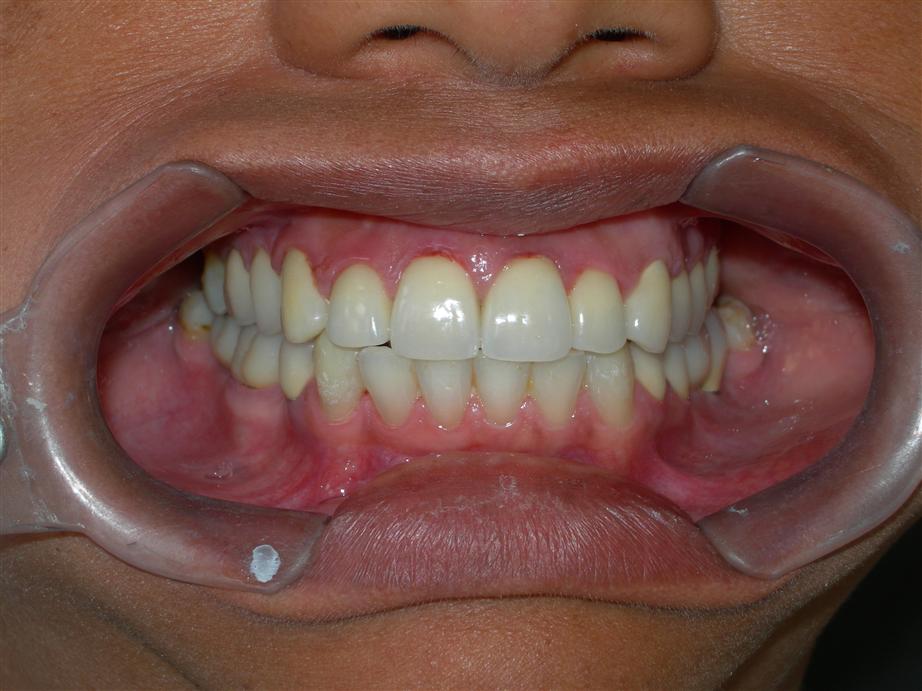

Caso concluído com próteses

metalocerâmicas cimentadas

Caso concluído com próteses metalocerâmicas cimentadas